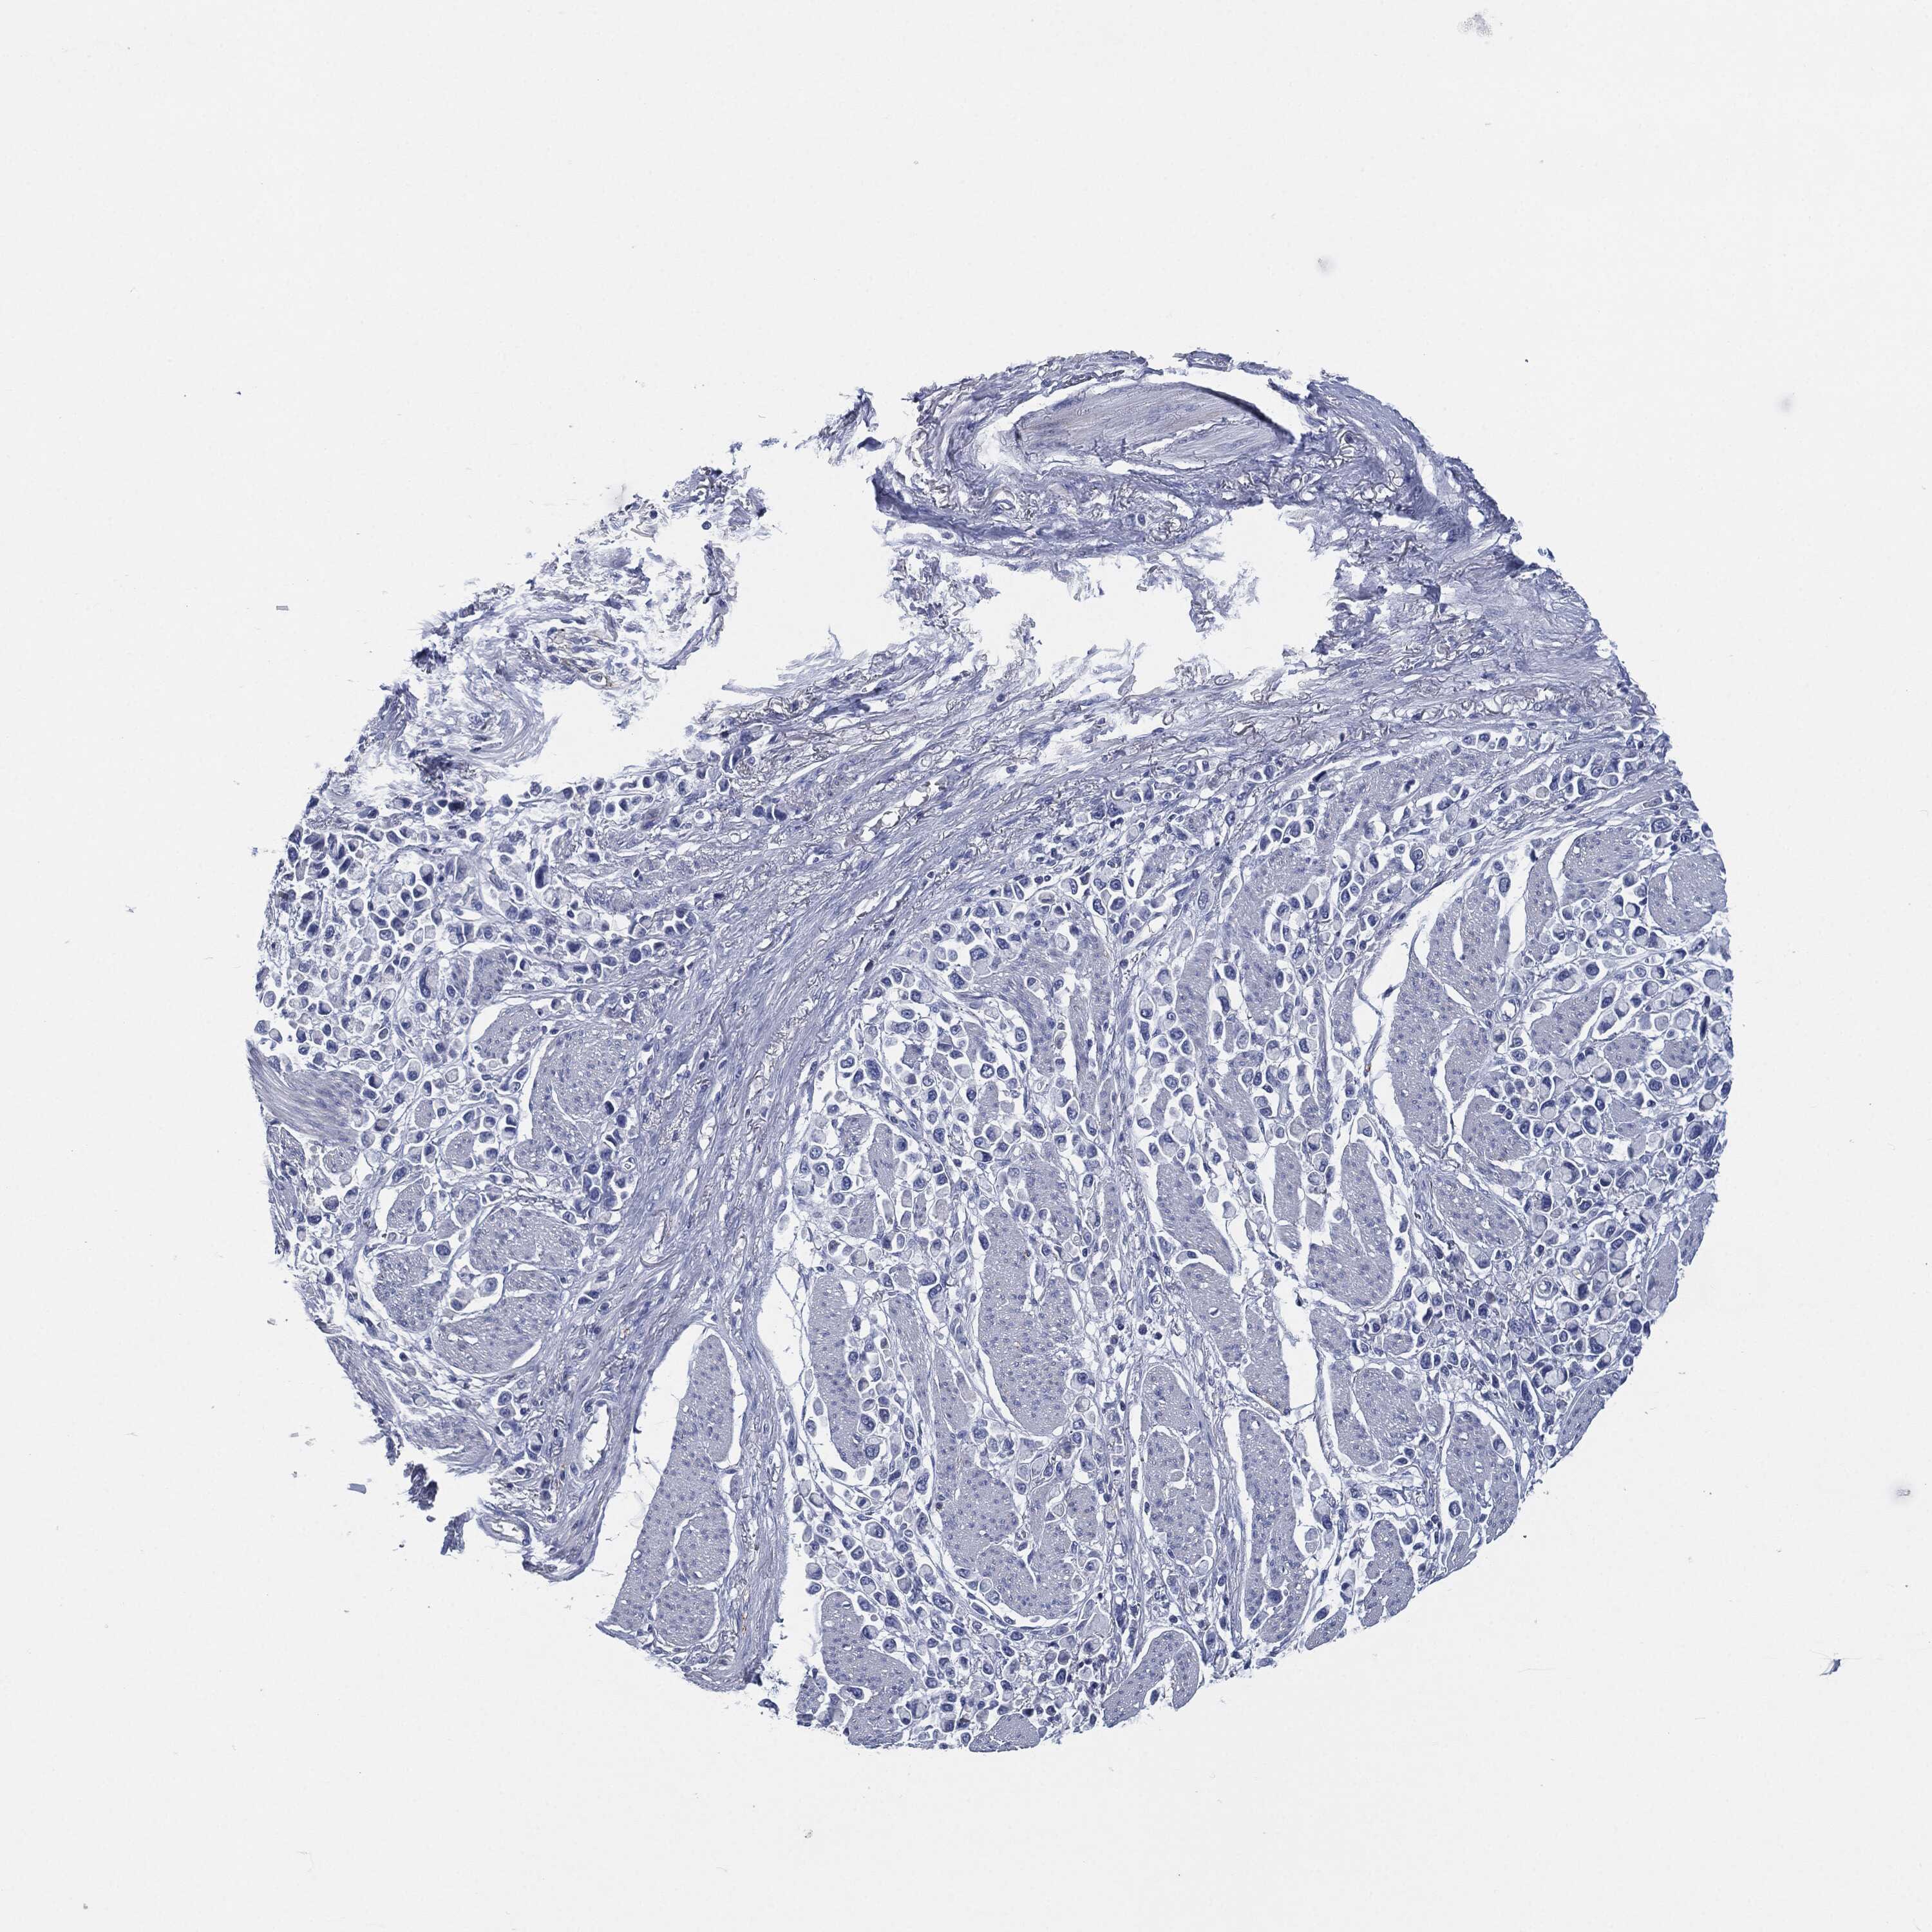

STOMACH CANCER - Protein expressioni

A mouse-over function shows sample information and annotation data. Click on an image to view it in a full screen mode. Samples can be filtered based on level of antibody staining by selecting one or several of the following categories: high, medium, low and not detected. The assay and annotation is described here.

Note that samples used for immunohistochemistry by the Human Protein Atlas do not correspond to samples in the TCGA dataset.

Antibody stainingi

Antibody staining in the annotated cell types in the current human tissue is reported as not detected, low, medium, or high, based on conventional immunohistochemistry profiling in selected tissues. This score is based on the combination of the staining intensity and fraction of stained cells.

Each image is clickable and will lead to virtual microscopy that enables deeper exploration of all samples and also displays staining intensity scores, fraction scores and subcellular localization as well as patient and tissue information for each sample.

Antibody HPA038936

Antibody CAB002420

Antibody CAB080304

Staining

Adenocarcinoma, NOS

Adenocarcinoma, High grade